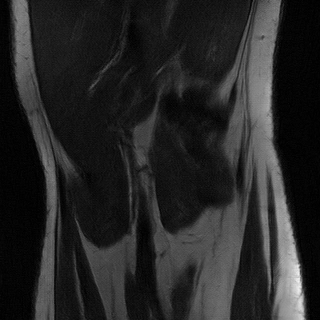

Accelerated MRI enhancement: The FastMRI [3] database consists of more than 1500 multi-coil diagnostic knee MRI scans and corresponding emulated single-coil data. Our experiments are based on a subset of nearly 800 coronal proton-density weighted scans without fat-suppression from the official train and validation single-coil releases. We remove of the patients for evaluation and split the remaining patients into input and target data. While the target domain consists of slices from fully-sampled MRI scans, we consider 4x acceleration (only of k-space measurements) for the slices by using the subsampling scheme discussed in [3, 4]. This yields 7.1k train slices for input and 6.9k for target. We are aware that enhancement of accelerated MRI can also be considered as a supervised task since generation of paired instances is feasible. However, this experiment should demonstrate possible applicability of the proposed framework to inverse problems in general.

In Table 2 we observe for the accelerated MRI enhancement task on FastMRI that our method UAPI significantly outperforms other benchmark on unaffected test data but gives modest accuracy when additional noise and perturbed pixels are added. Figure 4 shows the superior performance of CUT in terms of the PSNR metric for noisy data. This is quite interesting since that has not been the case for the previous modality propagation application. The task of accelerated MRI enhancement strongly differs from the other two applications. While the goal of modality propagation and MRI-to-CT synthesis is to come up with a completely new image, the aim of accelerated MRI enhancement is to improve quality of a already existing image. In fact, the methods cycleGAN, UGAC, gcGAN, PI and UAPI depend on a rather simple U-Net [34] implementation and a standard DCGAN critic [35] with the aim to demonstrate plausibility of different transfer approaches on easy-to-implement frameworks. The CUT method is a benchmark where the publicly available source code had to be used, consisting of a ResNet-based generator [11] and built-in data augmentation techniques that may better compensate for noisy input data. Nevertheless, our methods PI and UAPI seemingly achieve better results compared to the U-Net based benchmarks. We will take up investigation of robustness of our methods in combination with different network architectures as a future goal.

4.4 Qualitative Evaluation

In Figure 5 we analyze the prediction quality of our and compared approaches in a qualitative way. Considering modality propagation in MRI, we see that usage of uncertainty-aware patch invariance (UAPI) gives a better detailed weighting of the cerebrospinal fluid in the middle of the brain. In general, employing patch invariance yields better preservation of fine structures. This observation also applies to accelerated MRI enhancement. In particular, CUT and UAPI provide comparatively sharper knee images with more high-frequency details than the other methods.

Additional to improved accuracy we demonstrate the efficacy of estimating the scale maps with the proposed method. The input-dependent non-negative scale maps are derived from the second output branch , see (9). Indeed, the predicted scale maps are able to model uncertainty inherent from data. This can be observed in Figure 8, where in addition to the transferred images also the predicted scale maps and the absolute residuals between predicted and ground truth images are displayed. Obviously, uncertainty is relatively greater in regions with higher residual values. From the scale maps it can be deduced for which positions the generator is comparatively uncertain in its prediction, such as the cerebral cortex and eye sockets in head MRI or the lateral knee ligaments in knee MRI.